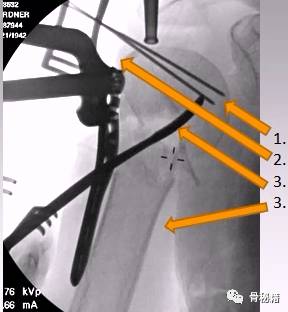

以钢板进行复位

然后用皮质骨螺钉进行提拉 完成肱骨近端解剖形态

解剖钢板与提拉螺钉的复位

需要注意 不要应用过度提拉 使得内侧肱骨距过复位

注意完成内侧支撑和内外翻的复位

在此病例中,为了复位良好,舍弃了肱骨近端与钢板贴服